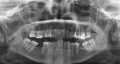

Хотела полечить зубы за рубежом на туристическом отдыхе в Европе, но возникли некоторые сомнения в компетентности европейского доктора. Был сделан панорамный снимок, и за 30 минут осмотра врач несколько раз поменял свое мнение от "зубы в ужасном состоянии, под корнями гной" до абсолютно противоположного. Конечно, я знаю, что зубы в сложном состоянии, но хотелось бы Вас спросить, видите ли Вы какой-то гной на снимке в деснах под корнями?

Есть ли возможность поставить мостик на зубы со стороны L, или попробовать вставить штифты в корни и сделать коронки? Или по данному снимку уже единственная возможность съемные протезы? Буду благодарна за объективную оценку ситуации, насколько это конечно возможно на расстоянии.

Я постараюсь дать вам полную консультацию по вашим зубам.

Начнем с сегмента L: 35 и разделенные уже корни 37 необходимо удалить, однозначно и даже думать нечего и через три месяца можно устанавливать имплантаты, как минимум 4 шт, на 38 на верхушке есть воспаление, диагноз периодонтит, необходимо пролечить.

Теперь сегмент R: также 46 зубе периодонтит.

На верхней челюсти так же перегрузка на 1.3, 1.7 зубе, слишком продолжительный мостовидный протез, недопустимый пролет для моста, а справа консольная конструкция, что так же является недопустимой.

В общем то все, проблем много, если вы в Москве, приезжайте мы составим вам правильный план лечения с успешным результатом!